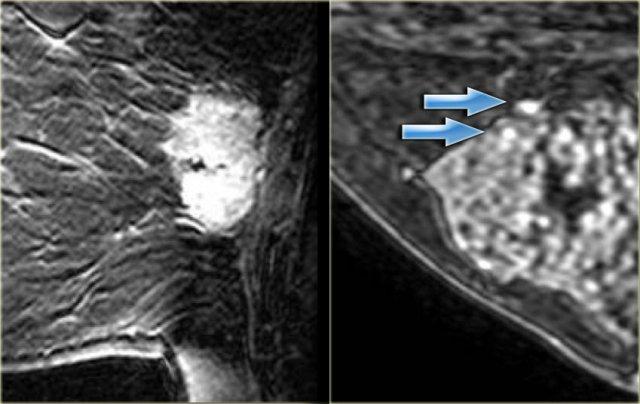

Ngấm thuốc dạng cụm

Ngấm thuốc dạng cụm là kiểu ngấm thuốc không tạo khối quan trọng nhất cần nhận biết.

Kiểu này có 60% khả năng là ung thư (thường là DCIS).

Bên trái là hai ví dụ về ngấm thuốc dạng cụm trong DCIS.